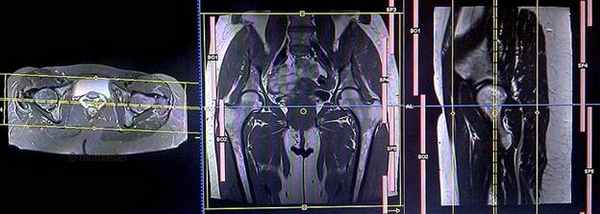

Локалайзер после проведения артрографии

Первично при планировании последовательности должны быть выполнены снимки в 3 плоскостях. Выдержка снимков менее 25 сек, с получением Т1-взешенных изображений низкого разрешения.

Серия Т1 vibe 3d с жироподавлением, коронарный срез 1мм, малое поле обзора (SFOV)

Планирование коронарных срезов на аксиальной плоскости; угловое расположение блока пересекает вертлужную впадину и головку бедренной кости пополам. Проверьте расположение блока на 2-х других плоскостях. Соответствующий угол должен быть получен в сагиттальной плоскости (рассекая головку бедренной кости и вертлужную впадину). Эти срезы должны полностью покрывать тазобедренные суставы, от седалищных бугров до уровня лобкового симфиза.